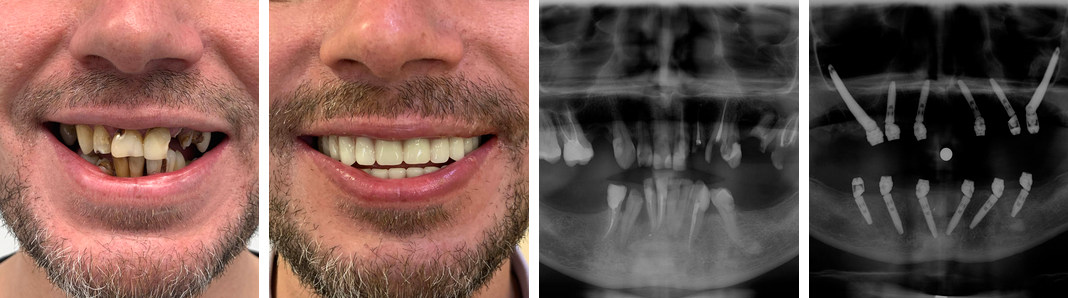

Имплантация зубов в Москве проводится качественно и безопасно. На сайте Центра americandental.ru вы можете записаться на бесплатную консультацию, ознакомиться с прайсом, посмотреть фотографии работ специалистов клиники.